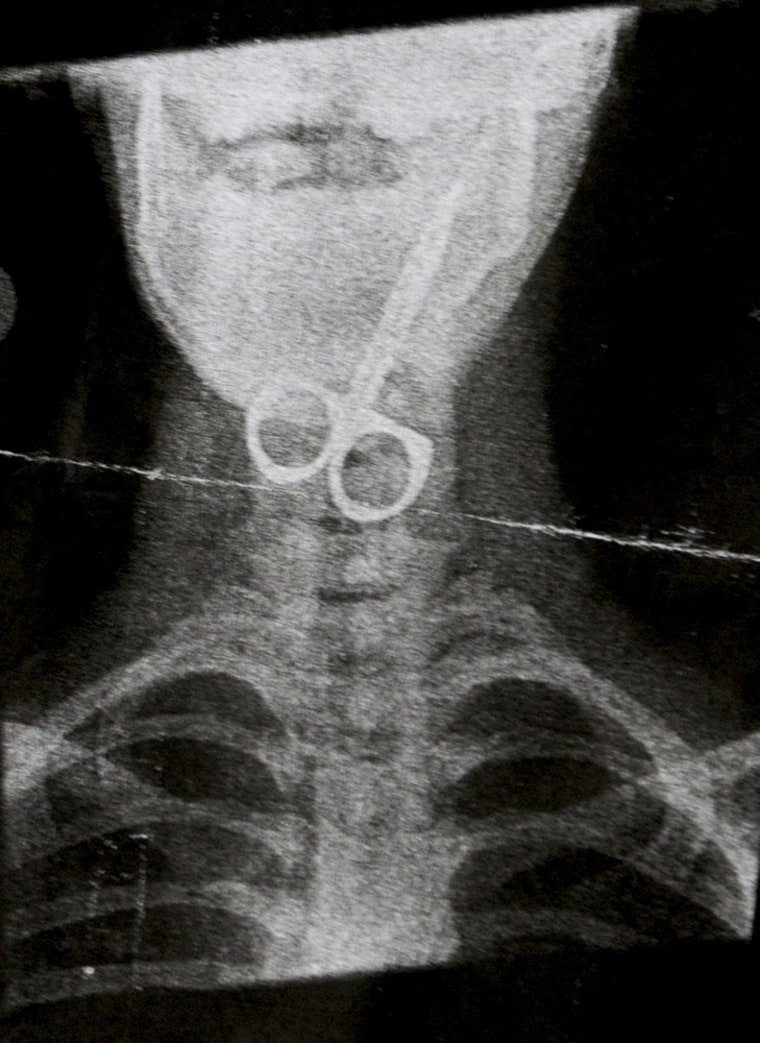

Проглотил болтик

Проглотил болтик 106 фотографий